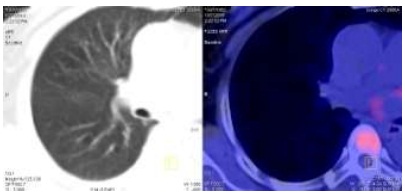

Hình 1.3. Nốt di căn phổi kích thước: 0,5cm, SUV=1,6.

Hình 2.4. Trước điều trị: Nốt mờ phổi phải

Hình 2.5. Sau điều trị: không thấy nốt mờ phổi